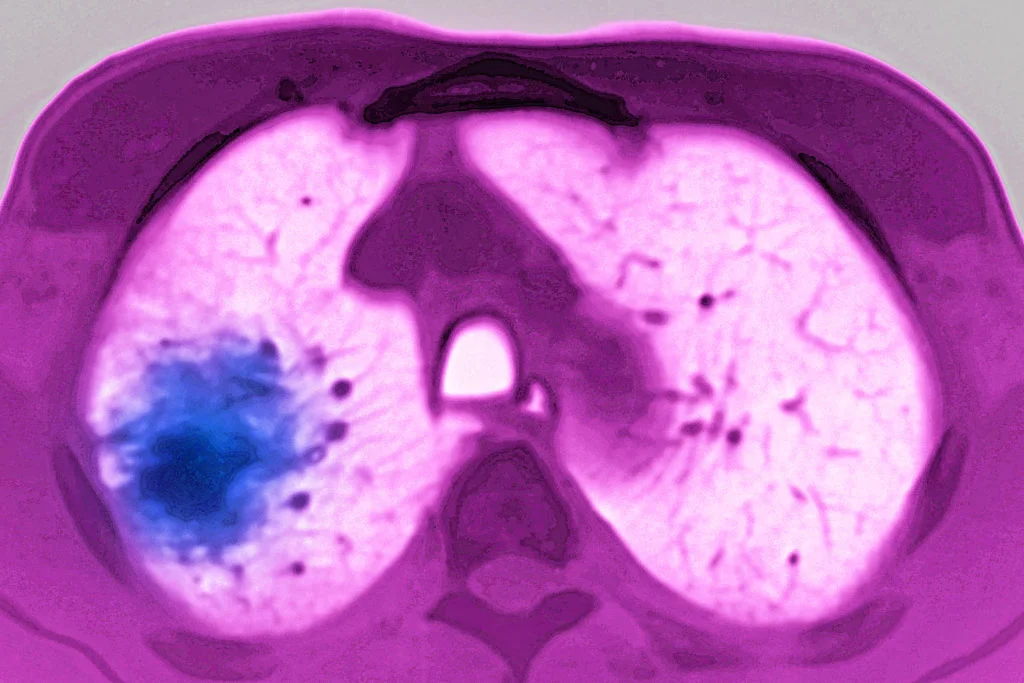

O câncer de pulmão é um dos tipos com maior incidência no Brasil. Relacionado ao uso ou exposição prolongada ao tabagismo, tem como principais sintomas a falta de ar, dores no peito, pneumonia recorrente, bronquite, escarro com sangue e tosse frequente. A doença é tratada com quimioterapia, radioterapia ou/e cirurgiaBSIP / getty images